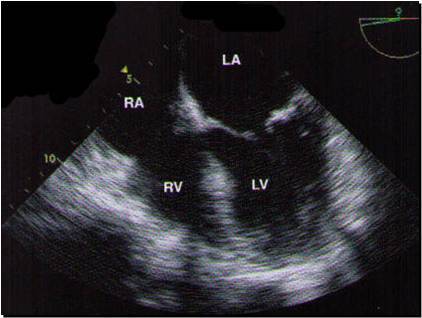

Here’s an easy 4 chamber view